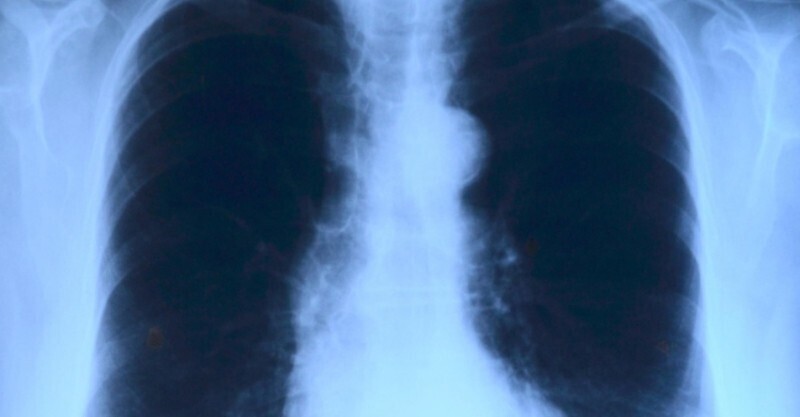

不抽煙無慢性病!29歲女「咳嗽一周」確診肺癌 醫生提醒「有這2種肺結節」要小心

延邊大學附屬醫院胸外科副主任徐正哲等人在《青年女性肺癌發病現狀及影響因素研究進展》一文中指出,青年女性肺癌的發生受多種因素影響,其具體機制尚未明確。除了吸煙、二手煙暴露、基因突變、雌激素,其他一些因素也被證實可增加肺癌的發生風險,如體重超標、飲酒、一些肉類食物和家族史等。以上因素相互作用,互相影響,與青年女性肺癌的發生密切相關。